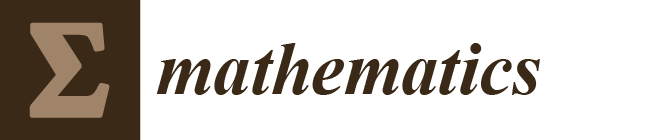

2. MDC Calculation

2.1. Building the Simulation Space from Mammograms